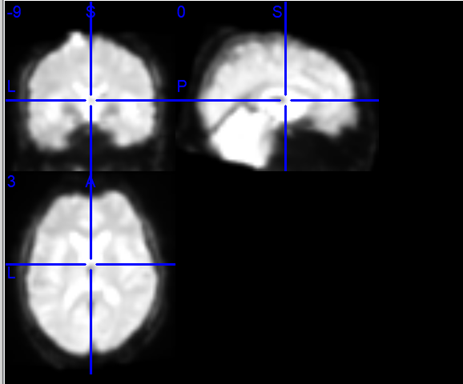

后续需要对图像进行分析时,如果没有选Add mean back,观察到的图像是下图这样的:

因为没有把均值加回来,看到的都只是差异值,根本看不出来图像的样子(但是对时间序列的计算不影响)。如果把Add mean back选上加回来之后,图像才会变回来:

只有这种完整的功能图像才能够进行下一步针对图像的分析。